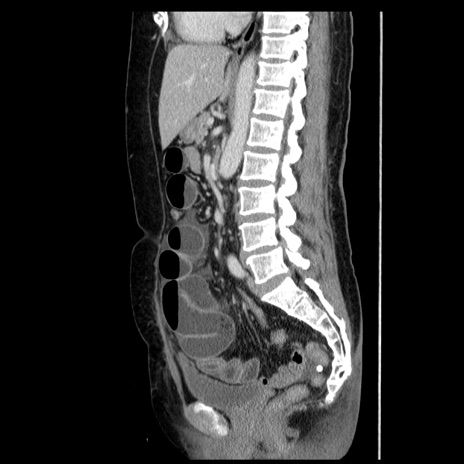

症例6(矢状断像)

【症例】50歳代女性

【主訴】下腹部痛

【現病歴】本日朝より下痢2回あり。 昼食を食べた後、嘔吐3回、下腹部痛認め、症状軽快せず、当院救急搬送。

最終食事:本日昼(生ものなし)。 昨日の夜、刺身を食ぺたとのこと。周囲に同様の症状の者なし。普段、排便は毎日あるとのこと。

【既往歴】卵巣癌術後(8年前に当院で卵巣摘出)

【身体所見】 意識清明、腹部:平坦、腸蠕動音→、やや硬、下腹部自発痛・圧痛あり、反跳痛あり、筋性防御なし。

【データ】WBC 16000、CRP 0.01